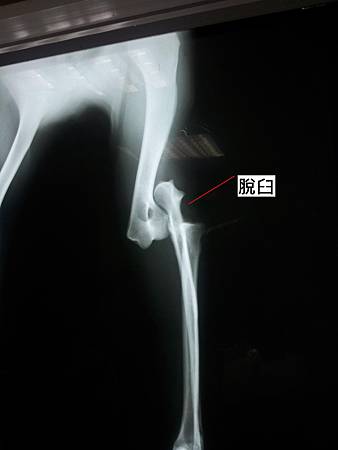

哈利來醫院時右手手肘向外脫出,無法著地。X射線檢查發現右側手肘脫臼需要進行韌帶重建手術。韌帶重建術是經由手術在原本韌帶生成處的骨頭兩端,先置入螺釘固定,再將人工韌帶緊綁於螺釘兩端,替代原來斷掉的韌帶。

上圖,可明顯看到手肘脫臼。

發生肘關節脫臼時,會出現急性的跛腳,患肢無法負重且呈現屈曲的姿勢,前肢會呈現外展且向外旋轉的情形。於X光下,側照可以看到肘關節的關節腔空隙看不清楚,有骨頭重疊的感覺。有時候創傷也可能造成肱骨髁狀突的骨折。